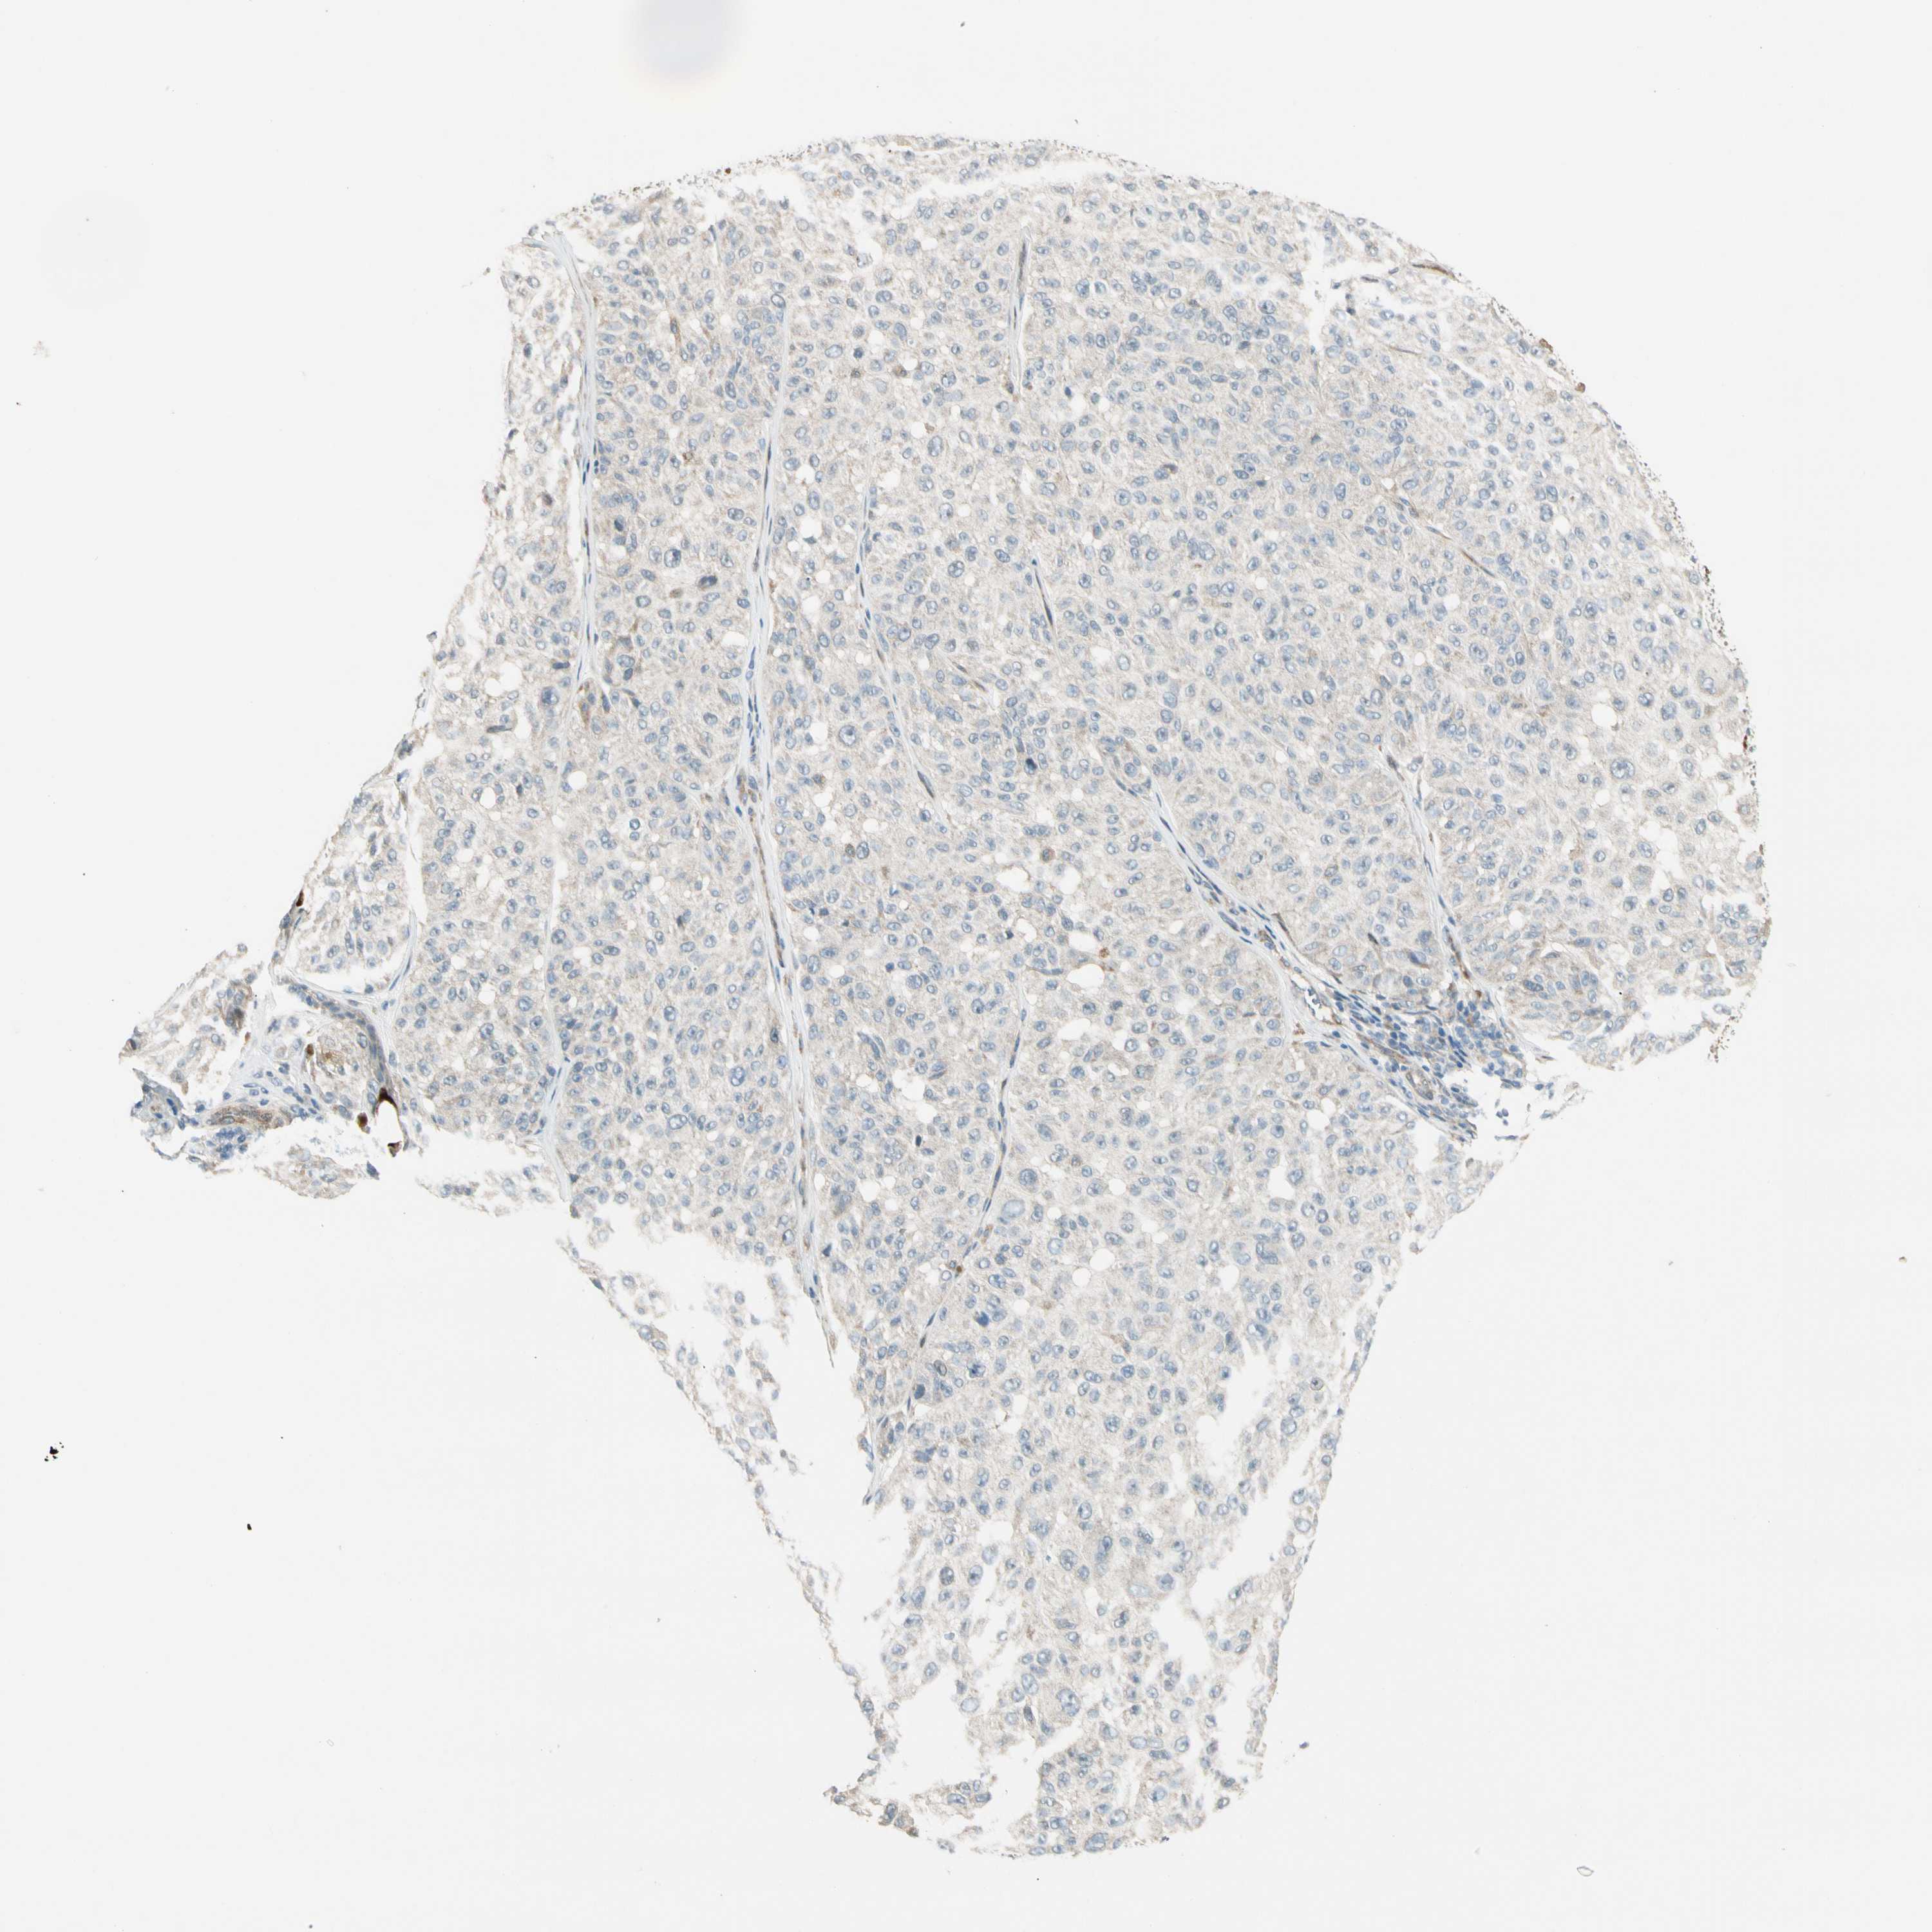

MELANOMA - Protein expressioni

A mouse-over function shows sample information and annotation data. Click on an image to view it in a full screen mode. Samples can be filtered based on level of antibody staining by selecting one or several of the following categories: high, medium, low and not detected. The assay and annotation is described here.

Note that samples used for immunohistochemistry by the Human Protein Atlas do not correspond to samples in the TCGA dataset.

Antibody stainingi

Antibody staining in the annotated cell types in the current human tissue is reported as not detected, low, medium, or high, based on conventional immunohistochemistry profiling in selected tissues. This score is based on the combination of the staining intensity and fraction of stained cells.

Each image is clickable and will lead to virtual microscopy that enables deeper exploration of all samples and also displays staining intensity scores, fraction scores and subcellular localization as well as patient and tissue information for each sample.

Antibody HPA008507

Staining

High

Medium

Low

Not detected

Intensity

Strong

Moderate

Weak

Negative

Quantity

>75%

75%-25%

<25%

None

Location

Nuclear

Cytoplasmic/membranous

Cytoplasmic/membranous,nuclear

Malignant melanoma, NOS

Malignant melanoma, Metastatic site